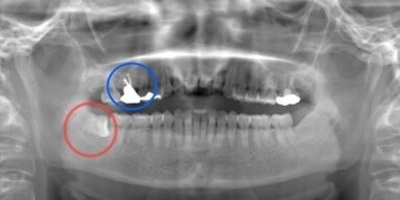

初診時レントゲン(パノラマ)

初診時パノラマX線写真と口腔内写真。

右上6に腫脹と排膿がみられた。

抜歯予定の歯と移植予定の歯

右上6(青丸)を抜歯し、右下8(赤丸)を移植することを計画した。

右上の抜歯後の治癒を待つため、抜歯の1ヶ月後に移植を行うこととした。